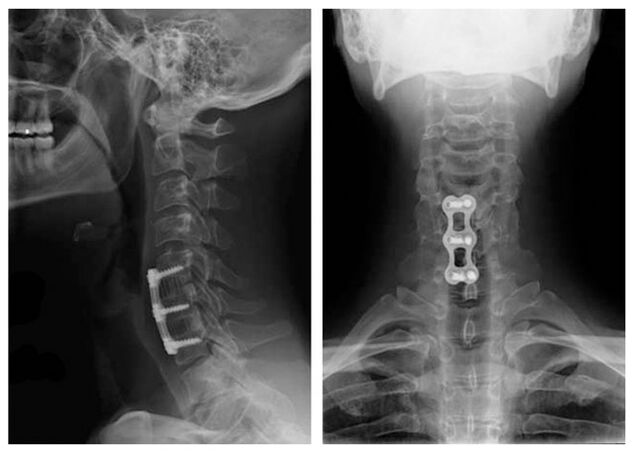

Cervikální osteochondrosis je léčena konzervativními metodami a léčba je vždy komplexní. Lékařská terapie je stejná pro osteochondrosu jakéhokoli oddělení: Používejte léky z určitých farmakologických skupin, ale výběr specifických léčiv z těchto skupin, dávkování, trvání příjmu je pro každého pacienta vybírána individuálně. X -ray obrázek krční páteře po chirurgickém ošetření obratlů C5 - C7 je doplněn dočasným nošením límce chanstz nebo jeho odrůd. Vzhledem k fixaci cervikálních obratlů se osteochondrosis děložní oblasti léčí rychleji. Toto další ortopedické zařízení pomáhá vyrovnat se s bolestí, normalizuje průtok krve cévy krku a zlepšuje obecný stav pacienta.